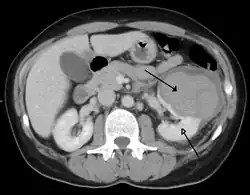

Abdominal trauma resulting in a right kidney contusion (open arrow) and blood surrounding the kidney (closed arrow) as seen on CT

Kidneys

A large hematoma (closed arrow) of the left kidney (open arrow)

The kidneys may also be injured; they are somewhat but not completely protected by the ribs.[6] Kidney lacerations and contusions may also occur.[13] Kidney injury, a common finding in children with blunt abdominal trauma, may be associated with bloody urine.[13] Kidney lacerations may be associated with urinoma or leakage of urine into the abdomen.[4] A shattered kidney is one with multiple lacerations and an associated fragmentation of the kidney tissue.[4]